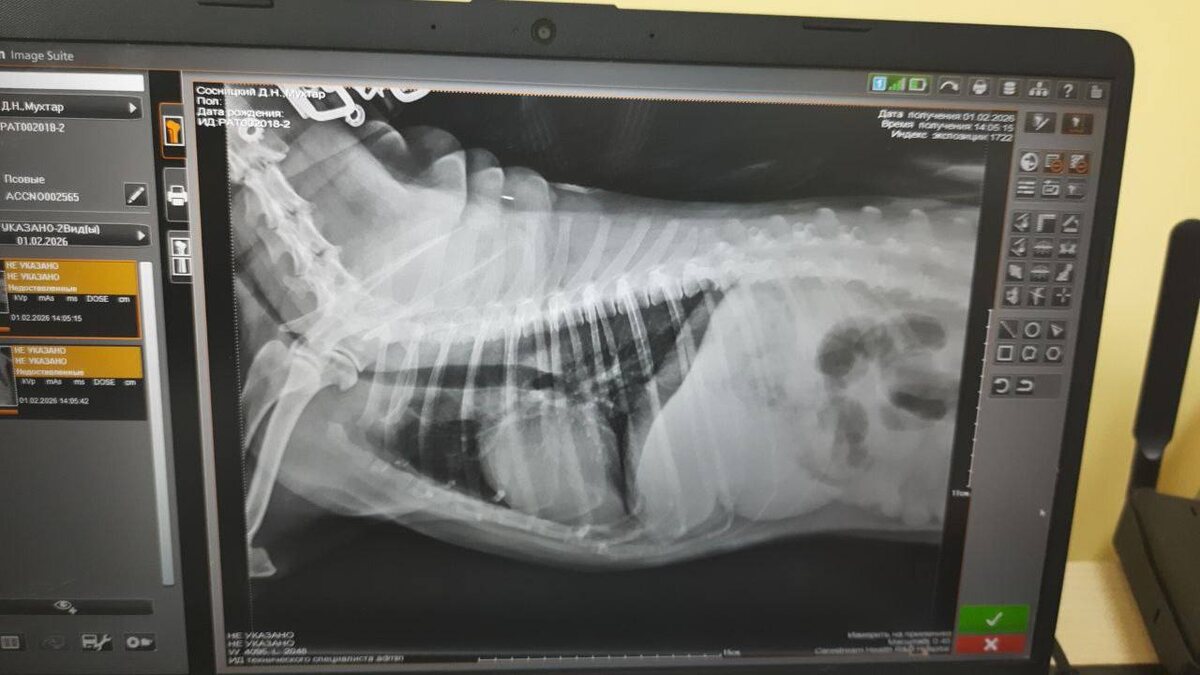

Улучшение по снимку есть

Но до конца все не прошло! Поэтому мы продолжаем лечиться 🙏 🤍 Спасибо всем, кто поддерживает!